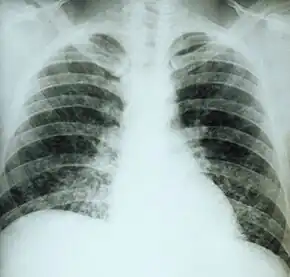

If symptoms of histoplasmosis infection occur, they start within 3 to 17 days after exposure; the typical time is 12–14 days. Most affected individuals have clinically silent manifestations and show no apparent ill effects. The acute phase of histoplasmosis is characterized by nonspecific respiratory symptoms, often cough or flu-like. Chest X-ray findings are normal in 40–70% of cases.[19] Chronic histoplasmosis cases can resemble tuberculosis;[20][21] disseminated histoplasmosis affects multiple organ systems and is fatal unless treated.[22]